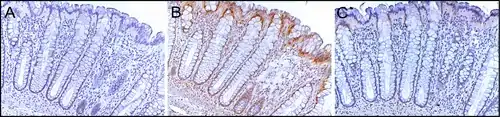

ERCC4 (XPF) in the normal colon

Sequential sections of the same colon crypt with immunohistochemical staining (brown) showing normal high expression of DNA repair proteins PMS2 (A), ERCC1 (B) and ERCC4 (XPF) (C). This crypt is from the biopsy of a 58-year-old male patient who never had colonic neoplasia and the crypt has high expression of these DNA repair proteins in absorptive cell nuclei throughout most of the crypt. Note that PMS2 and ERCC4 (XPF) expression (in panels A and C) are each reduced or absent in the nuclei of cells at the top of the crypt and within the surface of the colonic lumen between crypts. Original image, also in a publication.[31]

ERCC4 (XPF) is normally expressed at a high level in cell nuclei within the inner surface of the colon (see image, panel C). The inner surface of the colon is lined with simple columnar epithelium with invaginations. The invaginations are called intestinal glands or colon crypts. The colon crypts are shaped like microscopic thick walled test tubes with a central hole down the length of the tube (the crypt lumen). Crypts are about 75 to 110 cells long. DNA repair, involving high expression of ERCC4 (XPF), PMS2 and ERCC1 proteins, appears to be very active in colon crypts in normal, non-neoplastic colon epithelium.

Cells are produced at the crypt base and migrate upward along the crypt axis before being shed into the colonic lumen days later.[32] There are 5 to 6 stem cells at the bases of the crypts.[32] There are about 10 million crypts along the inner surface of the average human colon.[31] If the stem cells at the base of the crypt express ERCC4 (XPF), generally all several thousand cells of the crypt will also express ERCC4 (XPF). This is indicated by the brown color seen by immunostaining of ERCC4 (XPF) in almost all the cells in the crypt in panel C of the image in this section. A similar expression of PMS2 and ERCC1 occurs in the thousands of cells in each normal colonic crypt.

The tissue section in the image shown here was also counterstained with hematoxylin to stain DNA in nuclei a blue-gray color. Nuclei of cells in the lamina propria, cells which are below and surround the epithelial crypts, largely show hematoxylin blue-gray color and have little expression of PMS2, ERCC1 or ERCC4 (XPF). In addition, cells at the very tops of the crypts stained for PMS2 (panel A) or ERCC4 (XPF) (panel C) have low levels of these DNA repair proteins, so that such cells show the blue-gray DNA stain as well.[31]